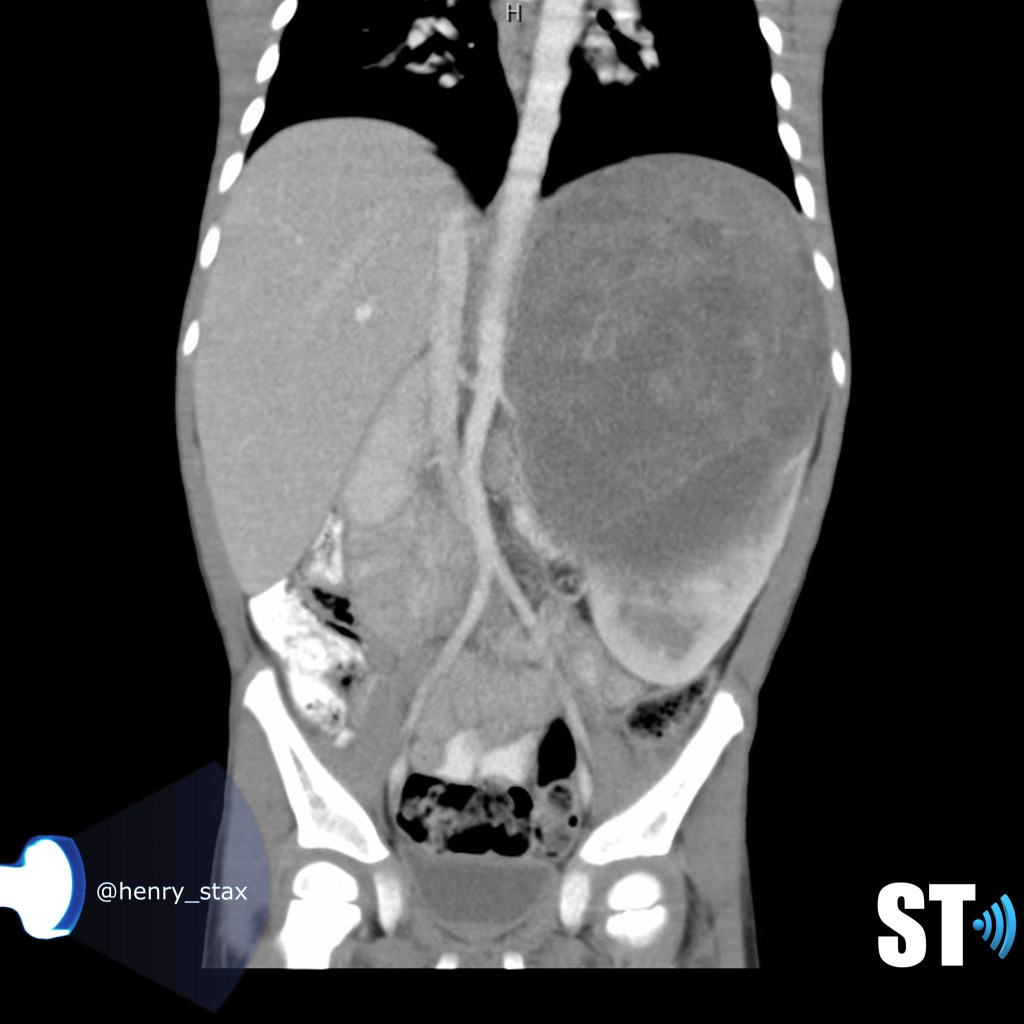

ADPKD

In Autosomal Dominant Polycystic Kidney Disease (ADPKD) the kidneys are normal at birth with cysts developing overtime. By age 30 years, approximately 68% of patients will have visible cysts by ultrasound. Eventually, virtually all patients develop cysts. The disease is transmitted in an autosomal dominant pattern, meaning you only one abnormal gene from one parent.

One abnormal gene from one parent

- Adult

- 4-10% of all cases of ESRF

- Kidneys appear normal early on

- Liver, pancreas and spleen cysts